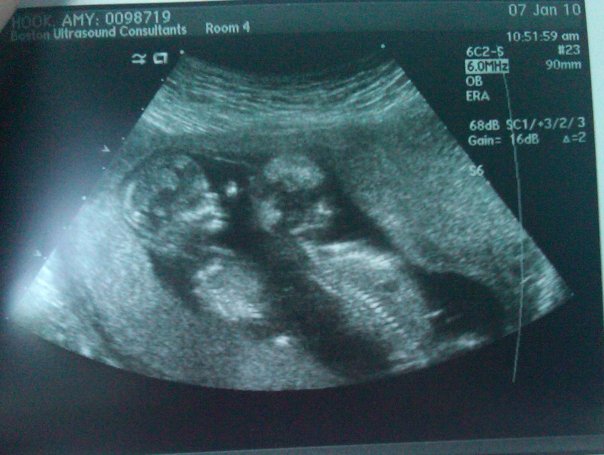

Some many weeks later, Amy went to the doctor again and, lo and behold, there was something new in there.

Here’s the definition of superfetation courtesy of About.com: “the formation of a fetus while another fetus is already present in the uterus. It occurs when eggs from two separate menstrual cycles are released, as opposed to normal dizygotic twins where multiple ova are expelled in a single cycle. Although common in animals, it is rare in humans, but can result in a twin or multiple pregnancy where the fetuses display a marked difference in gestational development.”

In layman’s terms, you’re pregnant and then get more pregnant. Put another way, baby number four took up residence down there before baby number three had moved out.

Throughout the entire pregnancy, these two babies were markedly different sizes. They grew at the same healthy rate but Oliver was, simply put, older. He was, in fact, five weeks older, according to the doctors. When born, he was two-and-a-half pounds heavier than Theo. In the hospital, Ollie was consider full-term and little Theo treated like a preemie. He weighed less than a bag of sugar and wasn’t much bigger.